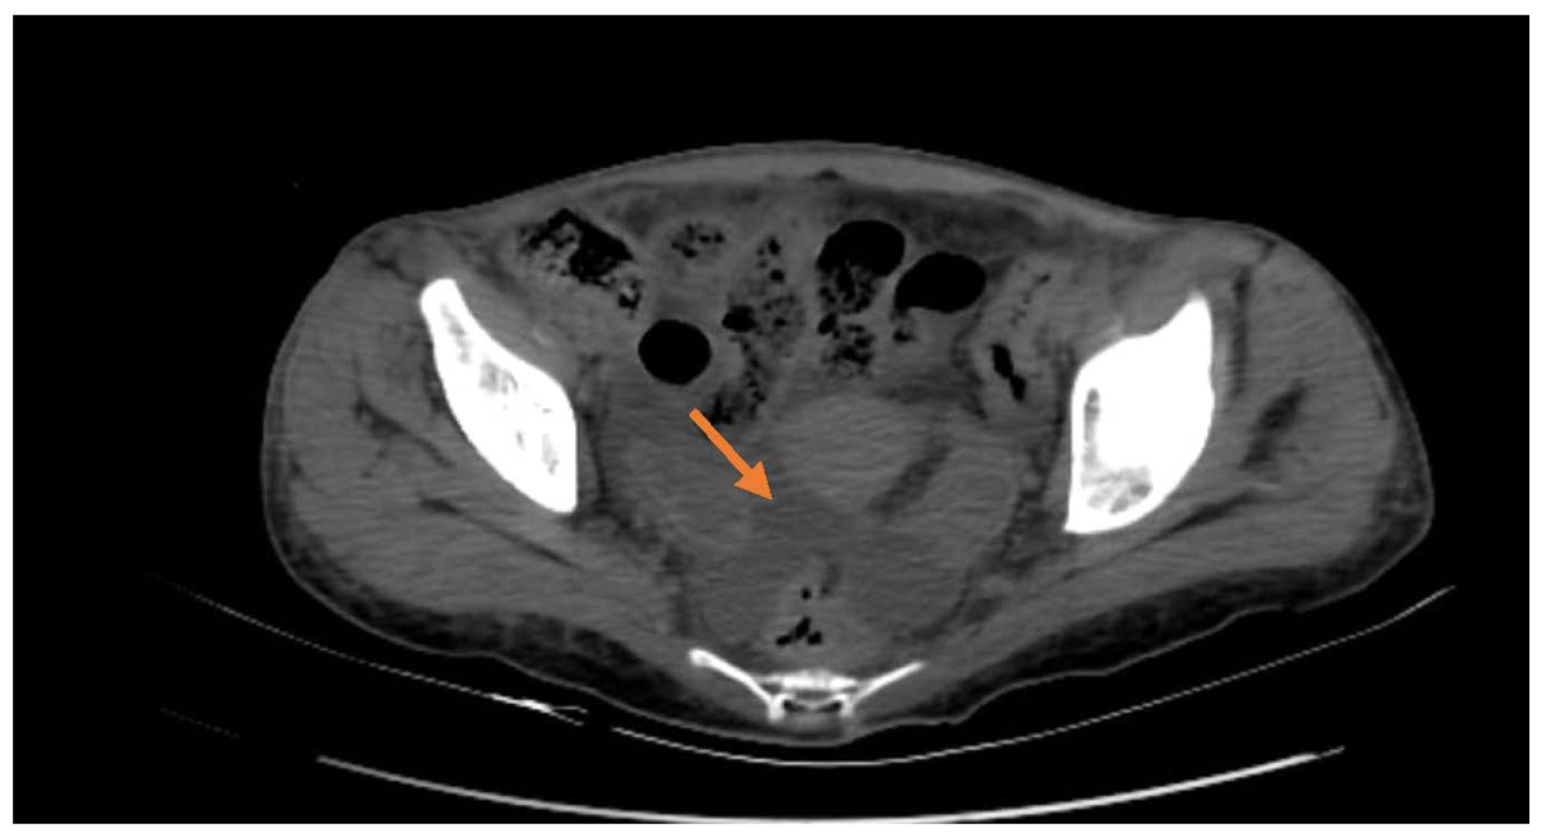

2. Case Presentation